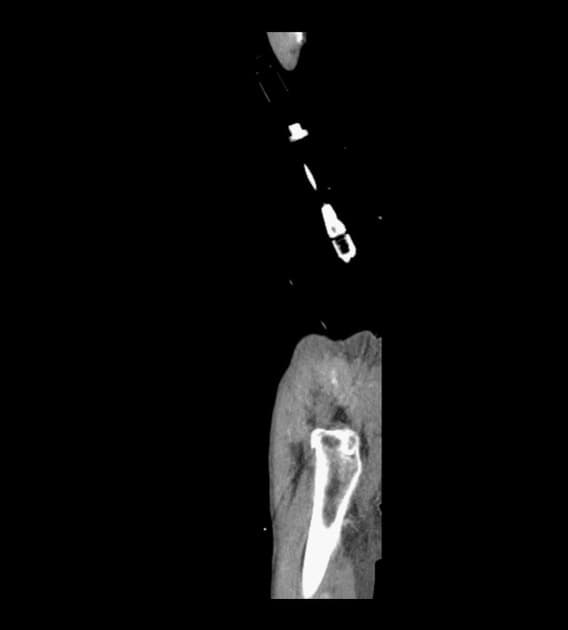

- Chụp cắt lớp vi tính lồng ngực cho thấy một tổn thương phát triển rộng và xâm lấn tại tim, khu trú chủ yếu ở tâm nhĩ phải, xâm nhập vào tĩnh mạch chủ trên.

- Ngoài ra, thấy các nốt đặc ở phổi, xuất hiện ở cả hai bên, số lượng nhiều, không đếm được, gợi ý tổn thương lan tỏa thứ phát (innumerable solid pulmonary nodules, bilateral, suggestive of involvement secondary dissemination).

Sau sinh thiết dưới hướng dẫn của cắt lớp vi tính, xét nghiệm giải phẫu bệnh cho thấy khả năng u tân sinh mạch máu, bao gồm u ác tính mạch máu dạng biểu mô (epithelioid angiosarcoma). Báo cáo miễn dịch hóa học xác nhận chẩn đoán u ác tính mạch máu (angiosarcoma).

U ác tính mạch máu tim (cardiac angiosarcoma)

- "Chẩn đoán hình ảnh cho thấy khối u xâm lấn, dị sản với di căn phổi thường gặp; chẩn đoán xác định cần sinh thiết và xác nhận bằng miễn dịch hóa học."

U ác tính mạch máu tim là một khối u ác tính hiếm gặp và rất ác tính có nguồn gốc từ tế bào nội mô mạch máu, chiếm khoảng 20-30% tất cả các khối u tim nguyên phát. Khối u chủ yếu ảnh hưởng đến người lớn ở độ tuổi từ 40 đến 60 và có xu hướng rõ rệt ở tâm nhĩ phải. Khối u thường biểu hiện bằng các triệu chứng toàn thân không đặc hiệu hoặc dấu hiệu suy tim phải do mô hình tăng trưởng xâm lấn. Trên hình ảnh học, khối u xuất hiện như một khối dị sản, xâm lấn vào tâm nhĩ phải và thường lan rộng vào các cấu trúc liền kề như tĩnh mạch chủ trên. Di căn theo đường máu, đặc biệt đến phổi, thường gặp ngay tại thời điểm chẩn đoán. Chẩn đoán phân biệt bao gồm các khối u tim nguyên phát khác như u myxoma, u lympho, cũng như các ung thư di căn. Chẩn đoán xác định dựa vào xét nghiệm mô bệnh học và các dấu ấn miễn dịch hóa học như CD31, CD34 và yếu tố VIII liên quan đến kháng nguyên. Tiên lượng rất xấu, thời gian sống trung bình dưới một năm, do bệnh thường được chẩn đoán muộn và đặc tính sinh học ác tính cao.